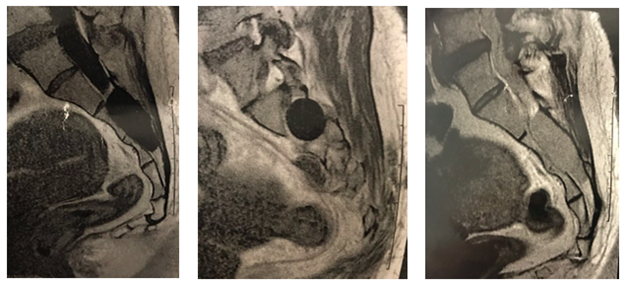

New MRI, gadolinium enhanced, showed an intramedullary constriction band, at the level of vertebrae S1-S2, with severe stenosis (Figure 3).

Figure 3 Gadolinium enhanced MRI shows important constriction band with canal stenosis in S1-S2.